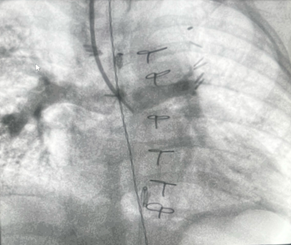

A 13-month-old 8 kg child with hypoplastic left heart syndrome (HLHS) status post Stage 1Norwood followed by bidirectional Glenn at 7 months of age presents for diagnostic cardiac catheterization for hypoxia with oxygen saturation of 60-65%. Superior vena cava (SVC) angiograms demonstrated a diffuse reticular pattern of the pulmonary vasculature, with rapid transit time of contrast into the pulmonary veins, and an absent capillary phase. No decompressing venovenous collaterals were identified on angiography. Indexed pulmonary vascular resistance (PVRi) on FiO2 = 100% and iNO 20ppm was 3.5 WU x m2.

The angiographic findings described -a diffuse reticular pattern, rapid contrast transit time from pulmonary artery to pulmonary veins, and absent capillary phase -are pathognomonic for pulmonary arteriovenous malformations (PAVMs), a known complication following superior cavopulmonary anastomosis (Glenn procedure).